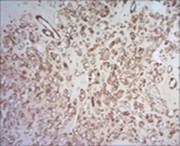

Multinodular tumour architecture is constituted by miniature, uniform, elliptical or spindle-shaped cells with scanty, eosinophilic, finely vacuolated cytoplasm and miniature, regular or hyperchromatic nuclei. Myxoid tumour matrix is envelops neoplastic cells configuring cords and strands. Nuclear pleomorphism is absent. Tiny foci of necrosis with focal chondroid differentiation may ensue6. Meningo-endothelial cells, physaliferous cells, rhabdoid cells, ductal differentiation and anaplastic cellular dedifferentiation is usually absent. Myoepithelial carcinoma displays nuclear atypia, elevated mitotic rate and extensive foci of tumour necrosis5. Figure 1, Figure 2, Figure 3, Figure 4, Figure 5, Figure 6, Figure 7, Figure 8.

Figure 8.Parachordoma demonstrating immune reactivity to vimentin 16.

Parachordoma is immune reactive to cytokeratin CAM 5.2 and glial fibrillary acidic protein (50%). A subset of tumour cells are immune reactive to CD99 and smooth muscle actin (SMA). Stroma is intensely highlighted with an alcian blue stain wherein staining intensity is reduced following hyaluronidase digestion. Tumour cells are immune reactive to epithelial membrane antigen (EMA), CK8/18, S100 protein, calponin (50%), vimentin, type IV collagen and CD117 6.